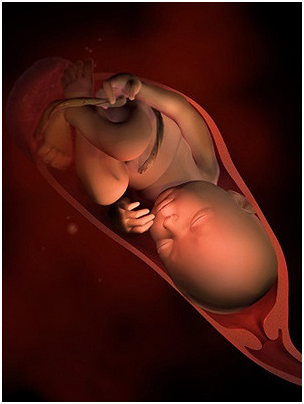

怀孕第38周恭喜准妈妈,从现开始你的宝宝已经是足月儿了,随时可能出来和你见面哦!你现在是不是...

怀孕第38周恭喜准妈妈,从现开始你的宝宝已经是足月儿了,随时可能出来和你见面哦!你现在是不是... -